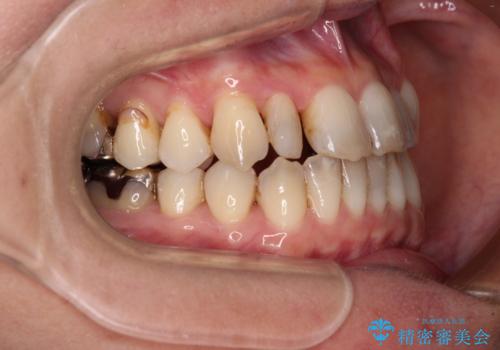

- 前歯の反対咬合を気にして来院された患者様です。

上顎骨の幅が下顎骨よりも小さいので、拡大装置により骨幅を広げて上下関係を改善すると同時にワイヤー矯正で反対咬合の改善を図り、その後インビザラインにて歯並びを整えることとしました。

上顎前歯の矮小歯は矯正治療の途中でオールセラミッククラウンを装着し、左右のバランスを整えることとしました。

急速拡大装置の使用により奥歯の咬み合わせが劇的に変わり、その変化を利用して反対咬合を改善することができました。

治療期間中は奥歯が咬み合わず、食事が取りにくいなどの不都合がありましたが、最終的にはきれいに整えることができました。